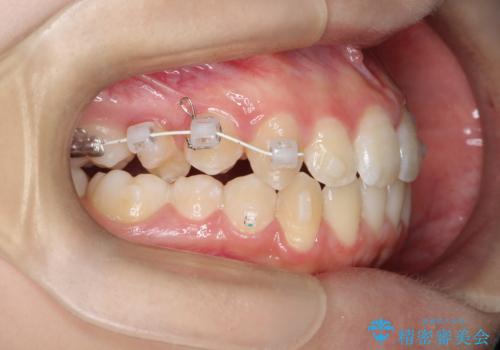

右上小臼歯の捻転を改善|インビザラインと部分ワイヤー矯正のコンビネーション治療

- 矯正装置

- インビザライン

- 右上の小臼歯が大きくねじれており、噛み合わせや見た目に影響を与えている状態でした。診察の結果、インビザライン単独では十分な回転が得られにくいと判断。そのため、基本的な歯列の移動はインビザラインで行いながら、部分的にワイヤー矯正を併用するコンビネーション治療を計画しました。

まず、インビザラインで歯列全体を整えながら、スペースを確保しました。その後、部分ワイヤーを装着し、右上小臼歯の捻転を効率よく改善。ワイヤーの力を活用することで、より確実に歯の向きを整えることができました。治療後は、「しっかり噛めるようになり、見た目も自然になった」と患者様にもご満足いただきました。